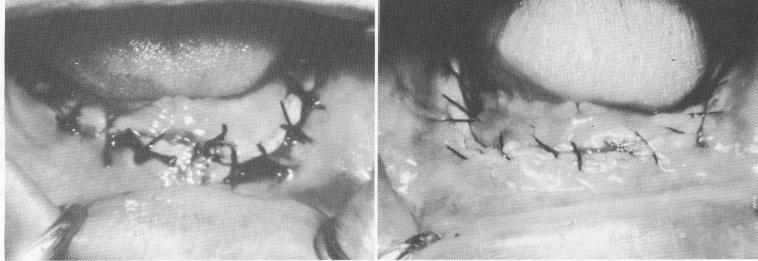

Fig. 14-46. A, Poor suturing. The sutures were made too far lingually, excessively stretching the buccal tissue. The knots also lie over the wound, irritating it and retarding healing. B, The sutures are too few, too irregular, and too far apart. Compare with Fig. 14-47, A and B.

3 Sutures made too far lingually, excessively stretching buccal tissue